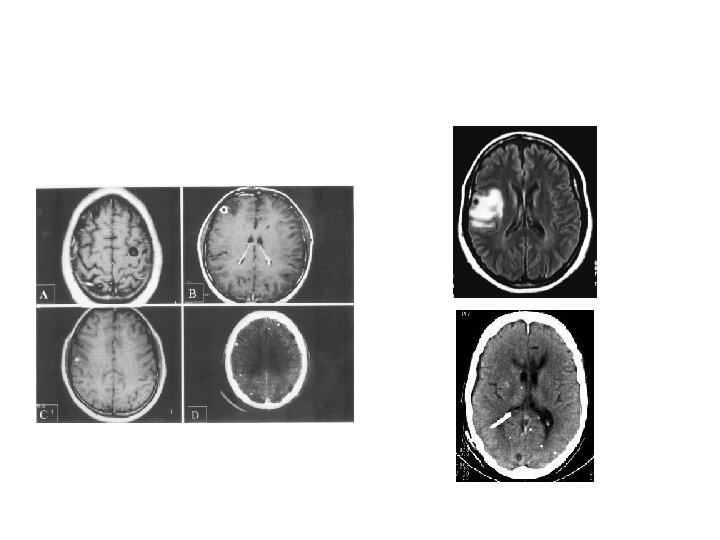

Seizures: Imaging - CT/MRI Has revolutionised the management of epilepsy Indications: focal features on exam, EEG Features of ICT Intractable However, now indicated in every case with unknown cause Not necessary in febrile/absence/BETS/ JME etc. Western studies - 30% abnormal (30 -50% of focal) -only 3% treatable Indian studies: Very high prevalence of granuloma like lesions –recent onset partial seizures in child/young adult 40% abn even after 1 st seizure indicated in every case